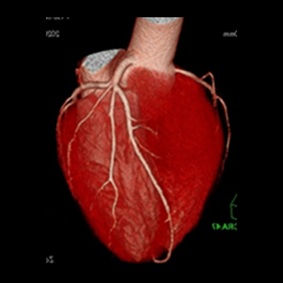

また、心臓のような動きのある臓器でも高精細な画像を得ることができます。

そして、画像再構成に新しい逐次近似的手法を用いることによって、画質を低下させることなく、

被ばく線量を通常の20~40%、最大で80%まで低減して撮影することができます。